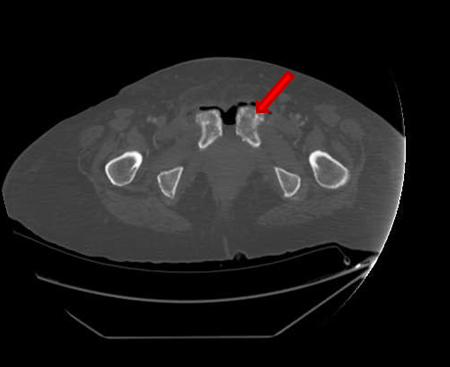

She presented on Emergency room suffering from fever, pelvic pain, and functional impairment of her right lower limb. Physical examination revealed bad smell vaginal flow and loss of strength on her right lower limb. Contrast computerized tomography and magnetic resonance images showed pelvic muscles impairment (Figure 1), inflamed bladder (Figure 2), and pelvic abscess lying from right psoas muscle to pubis bone, which presented radiologic signs of osteomyelitis (Figure 3) and (Figure 4).

Figure 3: CT scan image. Severe osteitis and osteomyelitis signs (cortical and medullary alteration) of bilateral pubic bones.

Figure 4: CT scan image. Severe osteitis and osteomyelitis signs (cortical and medulla alteration) of bilateral pubic bones.